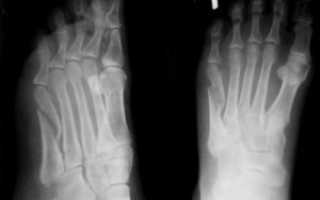

Снимок плюсневой кости делается в нескольких проекциях: прямой, боковой и полу боковой. Некоторые виды перелома могут потребовать повторного снимка, и особой укладки стопы пострадавшего человека.

Порой, на свежих рентгенограммах, которые сделаны в течение первых часов после нарушения целостности кости не видно вовсе. Все меняется через несколько недель, когда на повторно выполненном снимке, становится четко заметной линию перелома.

Это происходит из-за того, что края обломков поддаются резорбции.

Перед визитом к врачу вам будет выполнена контрольная рентгенография. С этими снимками вас осмотрит ваш лечащий врач и у вас будет возможность сравнить рентгенограммы до и после операции. Признаки сращения обычно становятся видны не раньше, чем через 6-8 недель после операции.